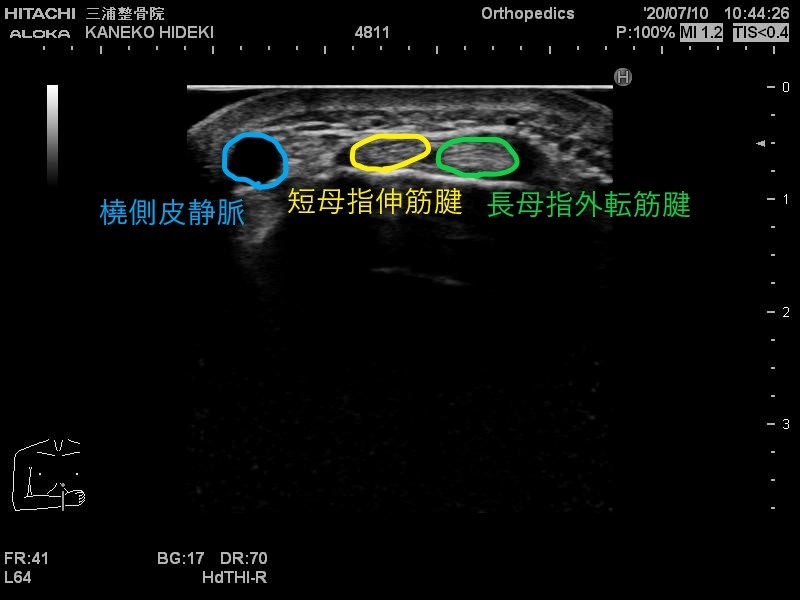

エコーではこのように写ります。